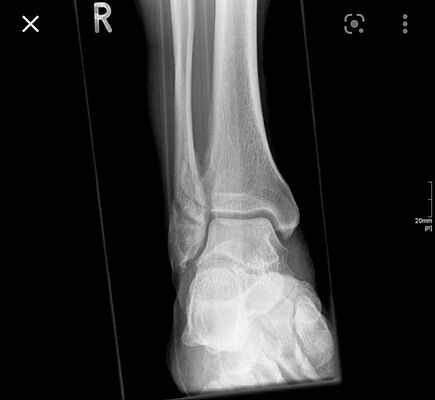

Nachdem sich der Weihnachtsmann am Heiligabend den Knöchel vermeintlich verstaucht hat, geht er sicherheitshalber zum Arzt. Dieser ordnet ein Röntgen an, da er vermutet es könnte auch etwas gebrochen sein.

Folgendes Röntgenbild wird dabei gemacht.

Welcher Knochen ist beim Weihnachtsmann gebrochen?

Lösung*: Fibula/Wadenbein